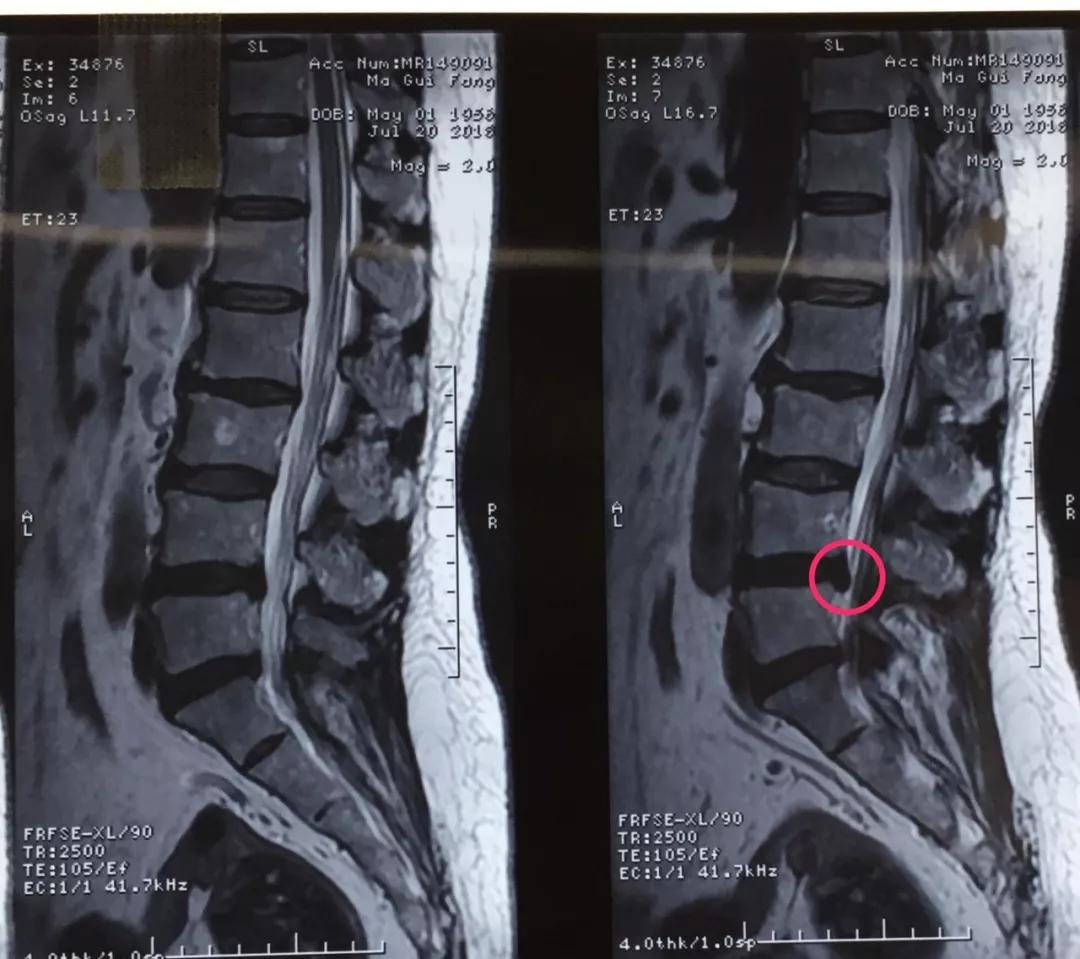

60岁的人生状态应该是退休在家,带着孙子孙女享受天伦之乐,而同样是60岁的马老太,被腰椎间盘突出症困扰了多年,稍微劳累就腰背酸痛,近几个月来又开始出现左下肢的过电样抽痛,抽的腿都抬不起来,家人带着马老太到医院做了检查说是腰椎间盘突出症,问了几家医院都说要来开刀手术,卧床两月,这下把马老太吓住了,一边是病痛折磨,一边是对手术的恐惧,正绝望之际,邻居建议马老太到按摩视频 郭华副院长的专家门诊看一下,马老太并没有抱太大希望,那么多医院都说要手术,估计治疗方案是一样的,手术是免不了了。到中心医院后,郭华副院长仔细地询问了马老太的病史,并进行了细致的查体,然后看了看片子,对马老太说:“你这个情况确实是腰椎间盘突出症,但是不需要全麻开大刀,局麻下1cm小口把椎间盘取出来就可以了,术后就可以直接下地走路了,而且你现在检查齐全了,当天住院、当天手术、当天出院,我们叫做——椎间孔镜日间手术”,马老太半信半疑的回家考虑了几天,最终马老太还是相信中心医院的实力,24日马老太入住骨一科后,郭华副院长、严少荣主任、姬钢主任医师中午共同为马老太局麻下实施了经皮椎间孔镜下髓核摘除术,手术共计一小时,手术完马老太抬腿就不痛了,郭华副院长告诉马老太,你这个情况完全可以出院走路回家了,可把马老太高兴坏了。

郭华副院长介绍:随着人口老龄化,腰椎间盘突出症的发病数量越来越多,而医学的进步也同样日新月异,传统的开大刀手术越来越少,我院开展的经皮椎间孔镜下髓核摘除术(PELD)是近几年来成熟起来地一种微创手术方式,局麻下不到一小时就可以取出压迫神经根的椎间盘,术后即刻解除疼痛下地走路,甚至可以做到日间手术(当日住院、当日手术、当日出院),医保报销后花费少,效果立竿见影,得到了广大患者的认可和好评。希望医学德进步给广大病患带来福音,希望我院的新技术能为更多的病人解除病痛。